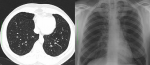

Case 1: presented in our outpatient clinic with complaints of difficulty in breathing, which began 5 days prior, associated with dizziness. There was no history of cough or chest pain or fever, he had a sample taken for COVID-19 just prior to presentation, which turned out to be positive and was admitted to the isolation centre. He had no known comorbidities. No abnormality was found on clinical examination. His chest X-ray (CXR) showed no evidence of pneumonia. He represented two weeks later following discharge from an isolation centre on account of chest pain, difficulty in breathing and fatigue. A computerised tomography (CT) of the chest also revealed no abnormalities. Full blood count, C-reactive protein (CRP) were normal. He was reassured and no further care was given (Figure 1).

Cases 2 and 4, with difficulty in breathing had oxygen saturations of 90% or less despite oxygen supplementation and this improved moderately on nursing prone. In index case 3, the clinical condition worsened and progressed to death despite mechanical ventilation. Hypoxaemia is reported to provide a robust risk factor for fatal outcomes and is associated with death in patients with COVID-19-associated pneumonia independently of age and sex [7]. It is also associated with higher neutrophil counts, D-dimer and CRP levels as well as acute inflammation of the respiratory system, caused by respiratory virus or secondary bacterial infection [7]. CRP and D-dimer were elevated in the more severe 3 of our index cases, also consistent with a moderate to severe inflammatory process [8]. Imaging for COVID-19 pneumonia mainly comprises chest radiography and computed tomography (CT). Our patients underwent X-rays and computed tomography scans. Chest radiographs are an initial and quick method of evaluating for significant lung abnormality. They may be less sensitive than CT, but are widely available, cost-effective and are suitable for primary hospitals which do not have CT machines as well as for the bedside examination of critically ill patients. Where there is high clinical suspicion of COVID-19, it is possible that a positive CXR may obviate the need for a CT [9]. Up to 89% of X-rays in COVID-19 may be interpreted as normal or mildly abnormal [10]. This is similar to findings in our patients as the x-ray in case 1 was normal while the chest X-ray in case 2 showed ill-defined bilateral alveolar consolidation with a peripheral and lower lobe distribution. It also excluded other pathology such as pneumothorax or pleural effusion. The other two cases did not have chest X-rays.

CT is the gold-standard for detecting the presence of lesions in the lungs, especially high-resolution CT, as it has no overlapping structural interference and can detect small lesions. It is useful for the diagnosis and differential diagnosis of COVID-19, monitoring treatment outcomes and early detection of other complications [3]. In the early stage, it shows multiple small patchy ground glass and interstitial changes, then develops into multiple ground glass shadows and infiltration with a peripheral distribution [3, 8], similar to the changes seen in our index cases 2 and 4. Ground-glass opacification is a slightly higher density, usually-rounded and blurred lesion in the lungs, where the pulmonary blood vessels are visible [1]. The ground-glass and/or consolidative opacities are usually bilateral, peripheral, and basal in distribution [1, 11]. This may be explained by viral invasion and replication in the bronchioles and alveolar epithelium causing inflammation and thickening of the alveolar wall with a distribution mainly around the lung and under the pleura [3]. In more severe cases, pulmonary consolidation may occur. Consolidation may be related to acute diffuse alveolar injury, including oedema, red blood cells and cellulose deposition. Thickening of the pulmonary interstitium or fibrosis may also be seen as stripes [3]. Pleural effusion and pneumothorax are rare [4]. Our cases run the gamut from mild to moderate to severe. Case 1 was a mild type with mild clinical symptoms and imaging findings showed no features of pneumonia. The chest CT manifestations of COVID-19 often presented patchy ground-glass opacities or mixed ground-glass opacities and consolidation, predominantly involving the periphery of both lungs, that can change rapidly [8]. Li et al. in a multicentre study in China showed that some patients with normal chest CT imaging could test positive for COVID-19 [8]. Cases 2 and 4 were of moderate severity with fever, cough, hypoxia and bilateral peripheral infiltrates, predominantly in the lower lobe in case 2. These findings are consistent with the findings described in other studies as the disease progresses [3, 8].

Figure 1: chest radiograph and CT images of case 1 on the 5th and 19th days of onset of symptoms respectively showing no evidence of pneumonia